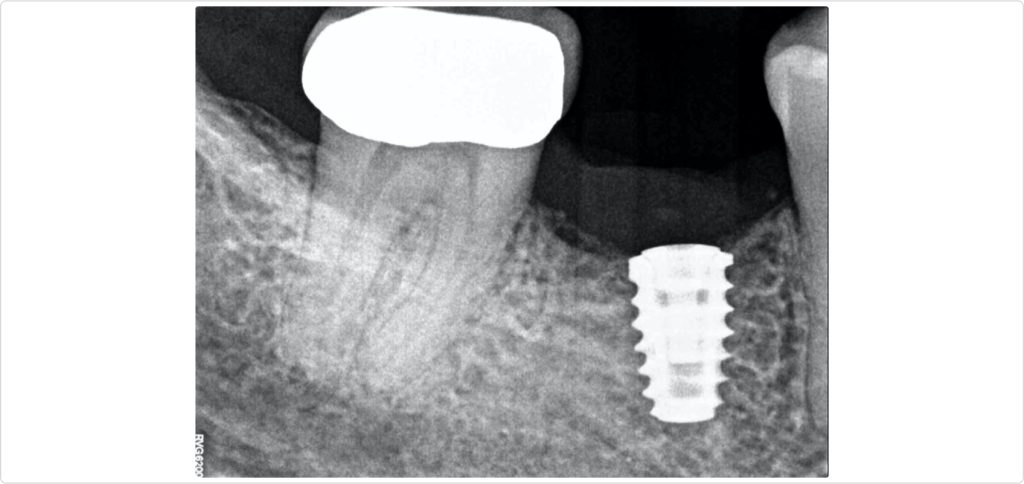

A CBCT scan was performed to evaluate the extent of the ridge defect and the anatomical position of the inferior alveolar nerve. The scan (Fig. 2) confirmed a significant defect and showed that the inferior alveolar nerve was positioned less than 10 mm from the alveolar crest, indicating a high-risk site for implant placement. This necessitated careful planning to avoid nerve damage during the surgical procedure.

The implant (4.6 by 7.5 mm) was placed in an ideal 3D position with an equal distance to the adjacent teeth, 1 mm subcrestal and centered buccolingual (Figs. 4a and 4b). However, because of the significant ridge resorption, approximately 4 mm of the buccal rough surface of the implant was exposed, resulting in a bone dehiscence.

A radiograph taken six months after the procedure (Fig. 7) showed satisfactory healing and bone integration around the implant, indicating successful osseointegration and stability of the grafted site. Clinically, a lateral view of the ridge (Fig. 8) revealed minimal keratinized tissue at the site, highlighting the need for further soft tissue management.

A radiograph taken one year after crown delivery (Fig. 13) demonstrated stable marginal bone levels around the implant, confirming the success of the comprehensive surgical approach and the stability of the peri-implant tissues. This radiographic evidence was corroborated by clinical observations, which showed no signs of inflammation or mucosal dehiscence around the implant site. The stability of the bone levels indicated successful osseointegration, a critical factor for the long-term durability and functionality of the implant.